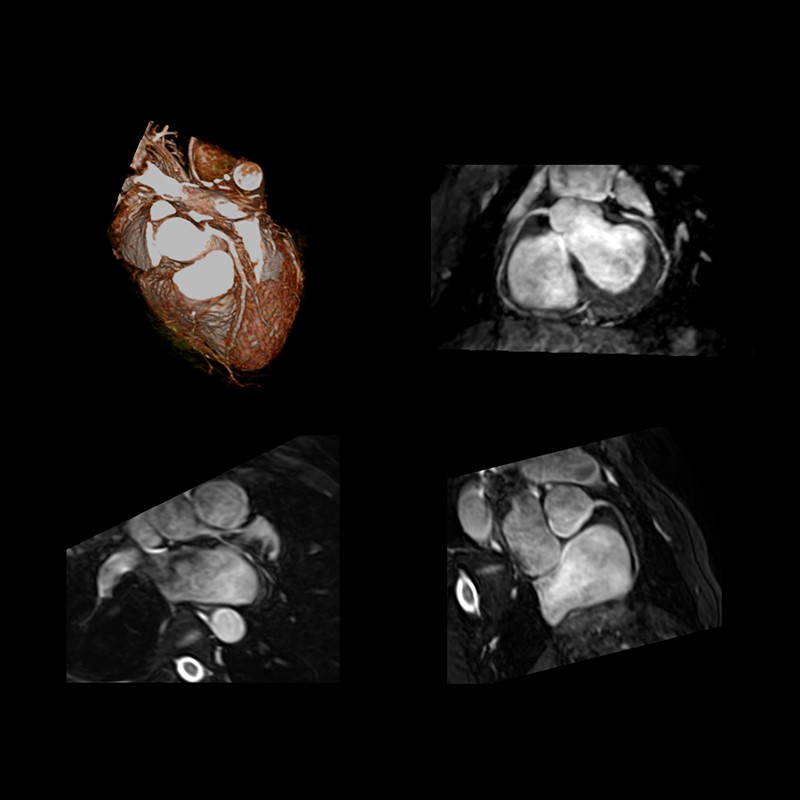

Безконтраста МР-візуалізація коронарних артерій (MRCA) виконан з використанням котушки для спини Octave SPEEDER™ Spine coil і 4-канальної гнучкої котушки flex SPEEDER™. Дані було оброблено завдяки можливостям програмного забезпечення консолі M-Power.